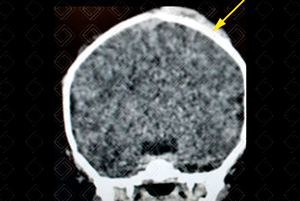

Texto alternativo para a imagem Figura 2. Créditos: Dra. Elazir Mota - Rio de Janeiro/RJ

Descrição das figuras 1 e 2: Tomografia de crânio revela um hematoma epidural biconvexo clássico à direita (seta vermelha). Há também um hematoma subgaleal laminar à esquerda (seta amarela). Abaixo (figura 3), foi realizada a reconstrução tridimensional do mesmo paciente, em busca de fraturas.

• Tomografia computadorizada do crânio (figuras 1, 2 e 3): Exam e de escolha no cenário de emergência por tratar-se de exame rápido e amplamente disponível. Co leção hiperdensa extra-axial e biconvexa . Deve-se procurar sempre por ar no interior do hematoma, que é um sinal de fratura associada do seio paranasal e mastoide, ou pelo sinal do redemoinho, uma heterogeneidade no interior do hematoma que sugere sangramento ativo. Sempre buscar por fraturas nas reconstruções tridimensionais (3D) e na janela óssea;